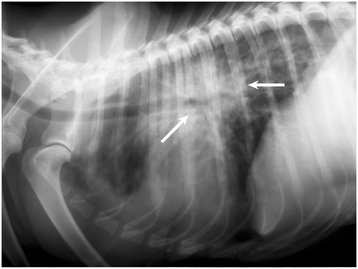

The aim of this review is to provide a comprehensive update on the biology, epidemiology, clinical features, diagnosis, treatment, and prevention of canine cardio-pulmonary angiostrongylosis. This cardiopulmonary disease is caused by infection by the metastrongyloid nematode Angiostrongylus vasorum. The parasite has an indirect life cycle that involves at least two different hosts, gastropod molluscs (intermediate host) and canids (definitive host). A. vasorum represents a common and serious problem for dogs in areas of endemicity, and because of the expansion of its geographical boundaries to many areas where it was absent or uncommon; its global burden is escalating. A. vasorum infection in dogs can result in serious disorders with potentially fatal consequences. Diagnosis in the live patient depends on faecal analysis, PCR or blood testing for parasite antigens or anti-parasite antibodies. Identification of parasites in fluids and tissues is rarely possible except post mortem, while diagnostic imaging and clinical examinations do not lead to a definitive diagnosis. Treatment normally requires the administration of anthelmintic drugs, and sometimes supportive therapy for complications resulting from infection.